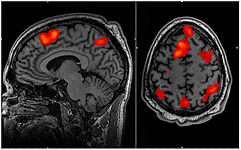

Functional MR[edit | edit source]

Functional magnetic resonance (fMR), along with the progressive development of statistical methods and computer technology, is developing as a means of visualizing the anatomical structures of the brain involved in the mechanisms of perception, motor control, and thinking. It therefore serves to functionally represent brain activity. The essence of the method is a change in blood flow and blood volume in the active area of the cerebral cortex (perfusion fMRI) and, unlike standard magnetic resonance imaging, it has the ability to detect dynamic signal changes caused by local fluctuations in oxyhemoglobin to deoxyhemoglobin ratio dependent on neuronal activity (BOLD - Blood Oxygenation Level Dependent). The non-oxygenated form of hemoglobin has paramagnetic properties and acts as a natural MR contrast agent, and thus in places with its higher concentration, magnetic inhomogeneities occur, due to the faster loss of energy of excited protons and thus greater local loss of radiofrequency signal. The active area of the brain, which consumes more oxygen, then provides a stronger signal than the surroundings.

During fMRI examinations with repeated scanning, images of the entire volume of the brain are acquired at rest, even during the active solution of tasks (response to a stimulus, movement of limbs, word formation, etc.). Changes in brain activity are measured from the difference between pairs of images taken at rest and during brain activity.

The Echo Planar Imagining (EPI) method is used for detection. This makes it possible to record the signal from the entire section (volume) after one or several radio frequency pulses by means of rapid changes in the magnetic field. The obtained signal is then divided into a finite number of samples, which have information about the signal from each section.

Functional magnetic resonance imaging allows you to specify diagnostics of some neurological and psychiatric diseases and provides options for planning surgical procedures.